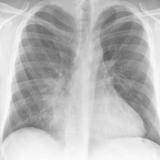

Case 1 PA